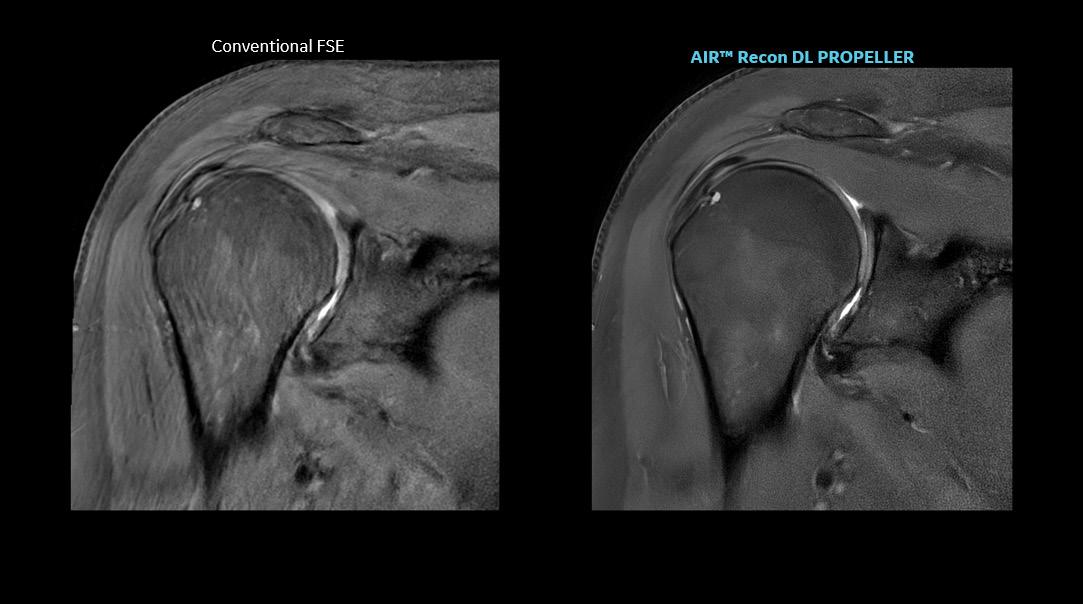

GE Healthcare has received FDA 510(k) clearance of its AIR Recon DL for 3D and motion-insensitive PROPELLER imaging sequences.

Loannis Panagiotelis, chief marketing officer for MR at GE HealthCare, said that his company has endeavored to address patient access to medical imaging and system productivity by increasing adoption of technological solutions that enable shorter scan times and sharpen image technology. AIR Recon DL, a deep-learning-based image reconstruction algorithm, removes image noise and artifacts from scans, leveraging raw image data to scan patients faster without compromising image quality.

Panagiotelis claimed the technology, which has been years in development, can sharpen images by as much as 60 percent and cut scan time in half.

Panagiotelis said. “We made [AIR Recon DL] available for all our systems – entry-level, mainstream, higher, new systems, legacy systems – and for all anatomies. That has been a grand success.”

Panagiotelis said that the improvements to throughput and efficacy of imaging that AIR Recon DL supports have expanded the reach of MR into studies that formerly were believed to be too complicated or time-consuming for the modality, including prostate screening, musculoskeletal imaging, and gerontological studies.

“It’s become simple and accurate, and that’s why this is taking off,” he said. “It becomes easy for the people to go and have these examinations. We believe it is impactful, but at the same time we are not compromising the procedure. The sharpness of these images is increasing because of the ability to combine

To date, GE HealthCare has sold more than 3,000 AIR Recon DL licenses, and installed some 2,000 systems; as of December 2022, the technology already had been used to scan about 5.5 million patients. With that level of adoption, Panagiotelis believes more patients will benefit from its advantages sufficient to address scanning backlogs, patient discomfort in the imaging suite, and even help make radiologists more comfortable during reads.

“We made sure that as many people as possible can benefit,”

studies with new types of contrast without compromising the overall duration of the scan.”

Taken together, the myriad technological advances that work to improve operational efficiency, simplify ease of use of the imaging systems, reduce acquisition time, and enhance workflow “all brings the costs down,” Panagiotelis said. “We go over this process multiple times a year, collect customer feedback, and try to define our products to meet their needs. There are different customer segments, but increasing patient access, clarity of scans — everybody needs these things.”

GE Healthcare states that 3D imaging provides for more clinical efficiency, allowing radiologists to eliminate the need for multiple 2D acquisitions—potentially leading to faster diagnosis.

AIR Coils are a technology in coils which are flexible, lightweight, and comfortable, enabling total freedom in coil positioning and handling during an MRI scan.